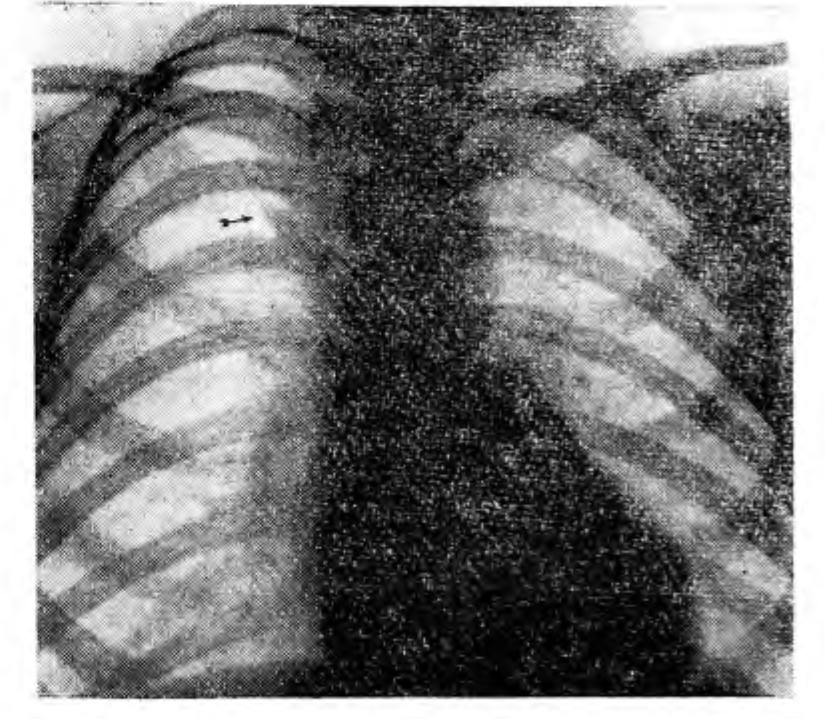

Рис. 1

Приводим два наших наблюдения.

М., 10 лет, 28/1-59 г. направлена с диагнозом «первичный комплекс в стадии уплотнения».

При рентгенологическом исследовании в первом межреберье справа, на уровне хрящевой части II ребра,

по правой окологрудинной линии, определяется небольшая каплеобразная тень величиной 0.5 X 0,8 см. Заостряясь по направлению вверх, она постепенно переходит в нежную дугообразно изогнутую линейную тень добавочной междолевой борозды, внутрь от которой располагается добавочная доля. Патологических изменений не обнаружено.